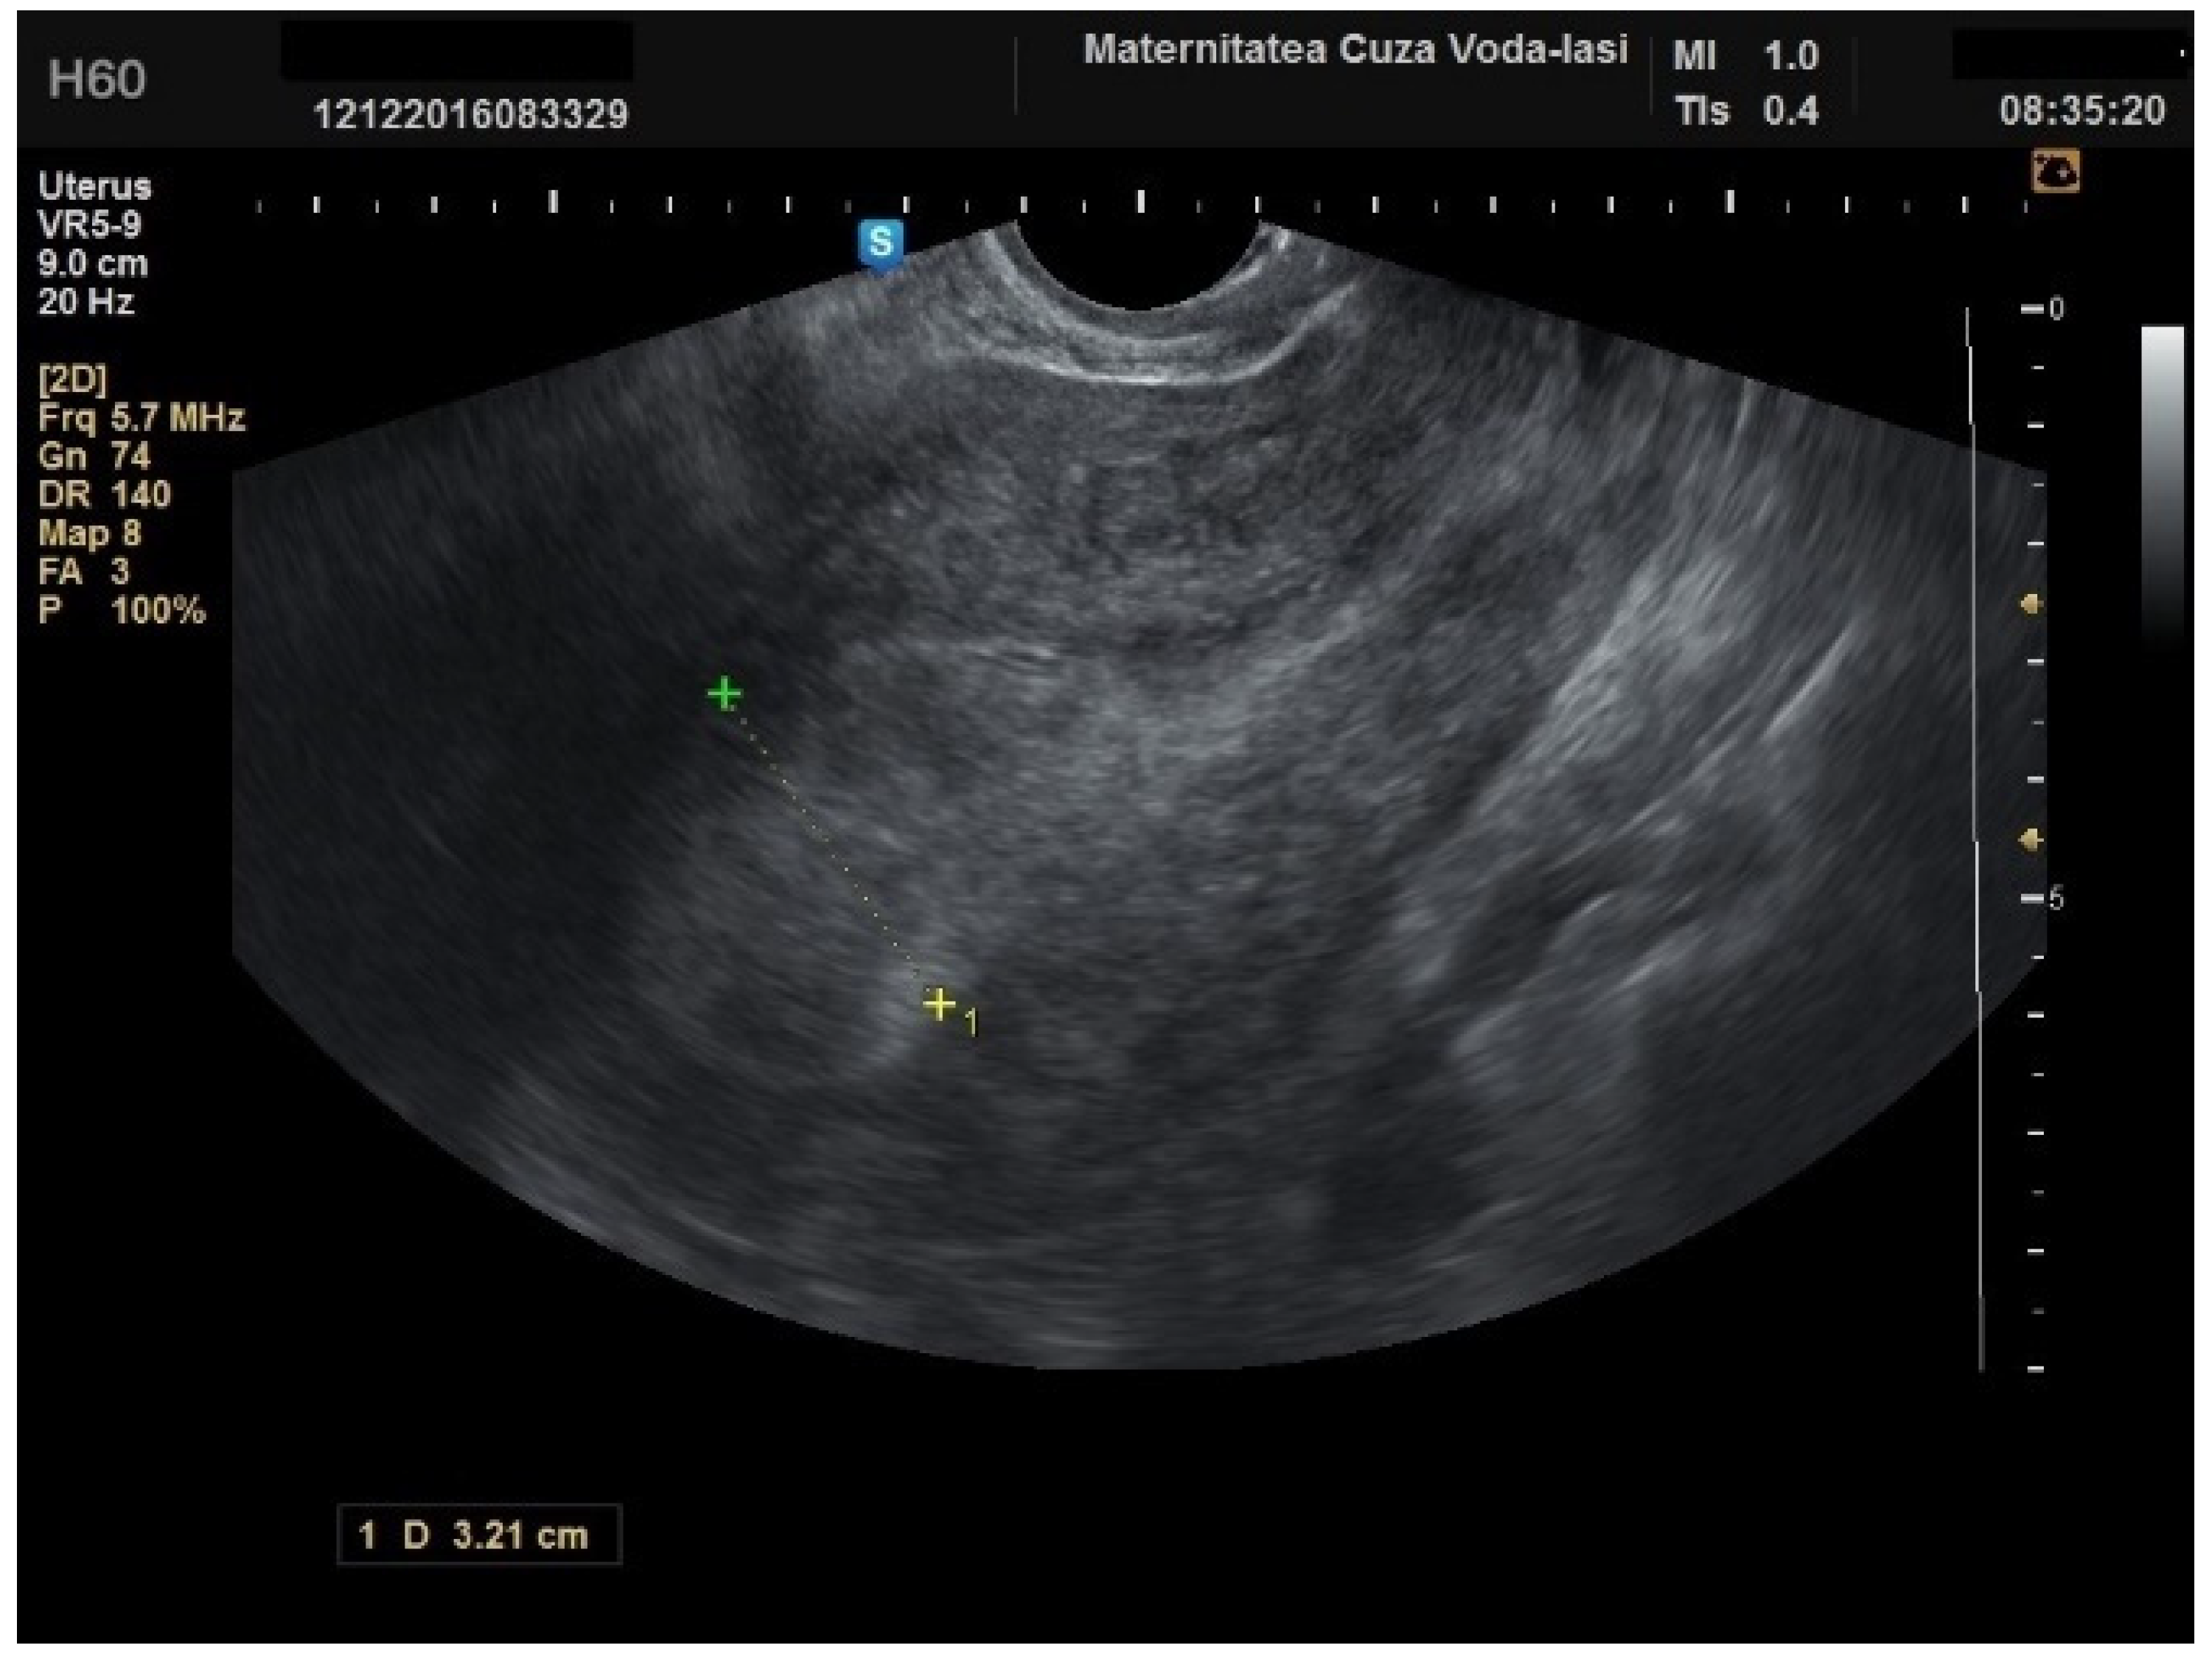

Figure 13. Ultrasound imaging in endometrial cancer: invasion of the posterior myometrium extending less than 50%—without vascularization.

We accurately assessed the depth of myometrial invasion, greater or less than 50%, for all patients with endometrial malignancy (Figure 13 and Figure 14) using a subjective method. Furthermore, the depth of myometrial invasion was also verified preoperatively with magnetic resonance imaging (MRI). In each case of endometrial malignancy, our pathology department appreciated the invasion by conducting a frozen section during surgery, as well as through the final paraffin-based histopathological exam.